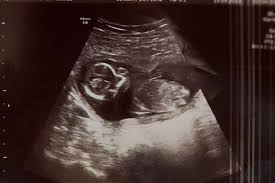

Estou de 6 semanas e fiz o ultrassom e constatou que a vesicula vetelinica hidropica esta com 20 cm o bebe esta com 03 cm o medico disse que talvez nem vai para frente a minha gestaÇÃo gostaria de saber mais informaÇÕes se vcs puderem me esclarecer desde ja muito obrigado. Suas emoções estão. Meninas na segunda irei fazer cm 6 semanas e 2 dias e queria saber de vcs no exame tem falando qual a potencia do aprelho onde vou faezr eh de 75mhz e queria saber se cm este aparelho jah vai dar pra ver tbm embriao coracaozinho entende.

Se puderem faezr isto por min agradeco muitoooo pq sei q muitas vezes a mamae ainda n ver pq conta da potencia do aparelho beijoooos. Nas imagens é possível ver os milimétricos dedos dos. Postem fotos das barriguinhas.